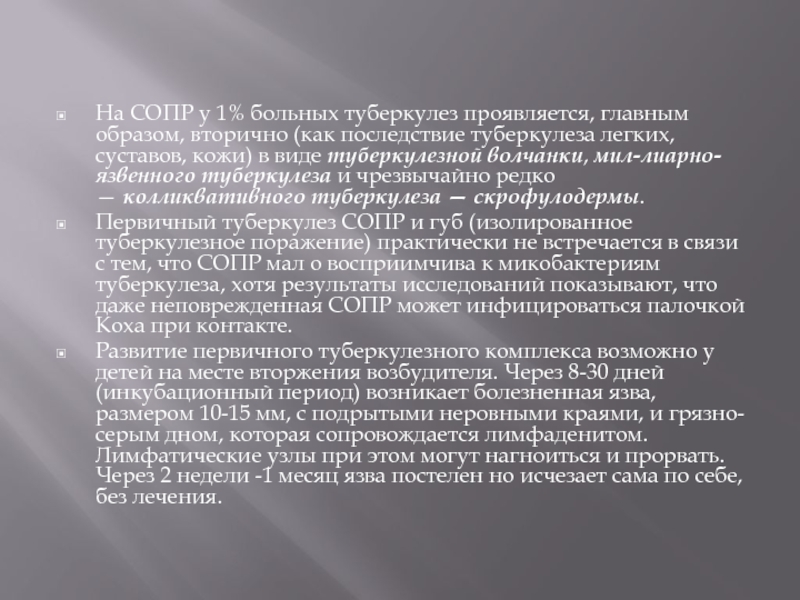

Симптомы и признаки туберкулеза: как распознать заболевание

Раздел: Визуальные уроки